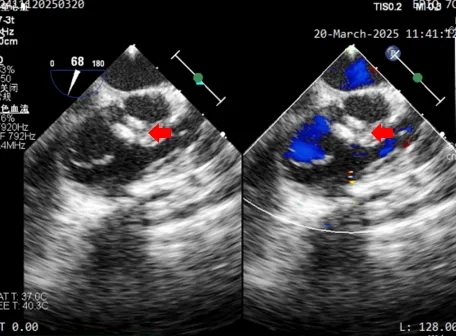

术后1个月随访,二维超声心动图及心脏彩色多普勒所见:

1、心房正位,心室右袢,房室连接正常,心室及大动脉连接正常。

2、各房室大小尚可。

3、室间隔、左室后壁、右室前壁心肌厚度正常。

4、房间隔完整,心房水平未见分流。

5、室间隔见封堵器回声,位置固定,伞面光滑,塑性良好,室水平未见分流。

6、左室流出道未见异常,主动脉瓣回声正常,启闭活动良好。

7、右室流出道心肌未见肥厚,肺动脉瓣回声正常,启闭活动良好,主肺动脉未见异常。

8、余瓣膜形态、结构及活动未见异常。

9、升主动脉、主动脉弓横部、主动脉弓降部未见狭窄,降主动脉血流正常。